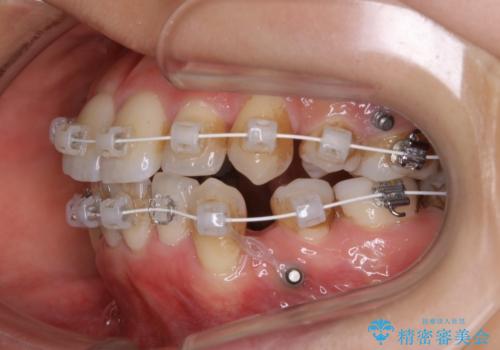

- ワイヤー(審美装置)

検査の結果、抜歯をすることでスペースを作って並べる方法が選択され、ワイヤー装置を用いた治療を開始することとなりました。

奥歯の上下のズレ等は軽度で、必要なスペースと抜歯により作られるスペースがほぼ等量だったため治療の単純化が計れ、大きな移動・見た目の劇的な変化に対して比較的早期での治療完了となりました。

- 審美装置/93万円(税込み) マイクロインプラント4本/8.8万円(税込み)費用は治療当時の料金となります